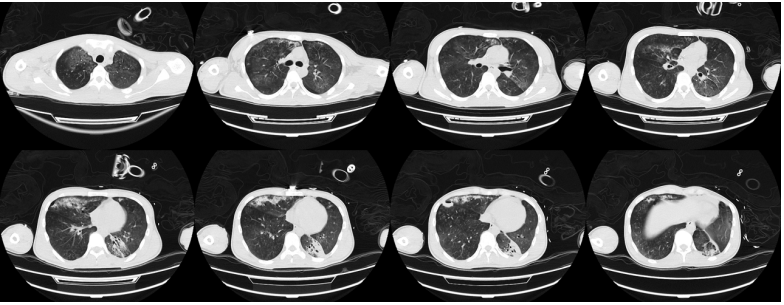

考虑到患者可能是病毒血症引起的全身非感染性炎症反应,于第7天决定选择甲泼尼龙(160 mg)给药1次,之后患者整体情况有所改善。密切监测其病原学,最终仅检出白色念珠菌,未在激素应用过程中出现曲霉感染。ECMO支持后(第8天)复查胸部CT可见双肺近乎完全实变,下肺尤为严重,肺内几乎没有有效通气(图4)

图片

图4  患者入院后胸部CT第8天